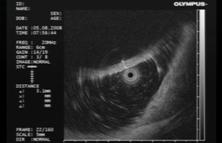

Ранний рак желудка. Общий эндосонографический критерий всех типов раннего рака желудка – это очаг неоднородного гипоэхогенного образования в пределах только слизистого слоя или занимающий слизистый и подслизистый слои стенки желудка (рис.1).

Рис.1. 62 года. Ранний рак верхней трети тела желудка.

Гистология – высокодифференцированная аденокарцинома:

а - визуальная картина РРЖ, подтип IIa; б – эндосонограмма РРЖ, подтип IIa, гипоэхогенное образование с признаками инвазии опухоли в подслизистый слой.